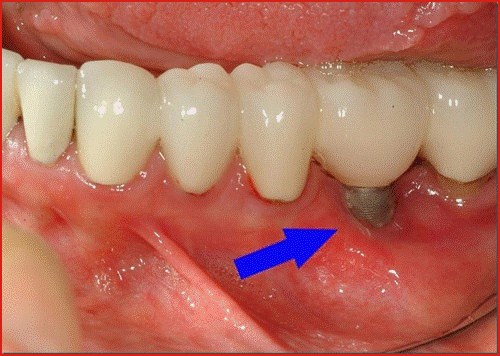

Thân implant bị dịch chuyển gây mất tích hợp xương

Implant có thể có những vi dịch chuyển trong thời điểm sau cấy do không đạt được sự ổn định sơ khởi ban đầu. Biến chứng này có thể do do nhiễm trùng cục bộ ở xương và nướu nâng đỡ thân implant hoặc nhiễm trùng toàn thân xảy ra ở những người bệnh tiểu đường. Hiện tượng này đặc biệt hay gặp trong những ca nhổ răng cấy tức thì – đây là 1 biến chứng sớm xảy ra do thiết bị máy móc thiếu chính xác hoặc trình độ chuyên môn của nha sĩ cấy ghép còn non tay.

Nhiễm trùng khu vực cấy ghép implant

Đây là một trong những biến chứng sau khi cấy ghép implant. Hiện tượng nhiễm trùng có biểu hiện đó là các mô xung quanh khu vực cấy ghép bị viêm sưng do vi khuẩn tấn công. Hiện tượng này có thể kéo dài trong nhiều tháng hoặc nhiều năm sau khi phẫu thuật, nhiễm trùng nặng sẽ dẫn đến viêm nhiễm, mất xương, cấy ghép thất bại nếu không được điều trị đúng cách.